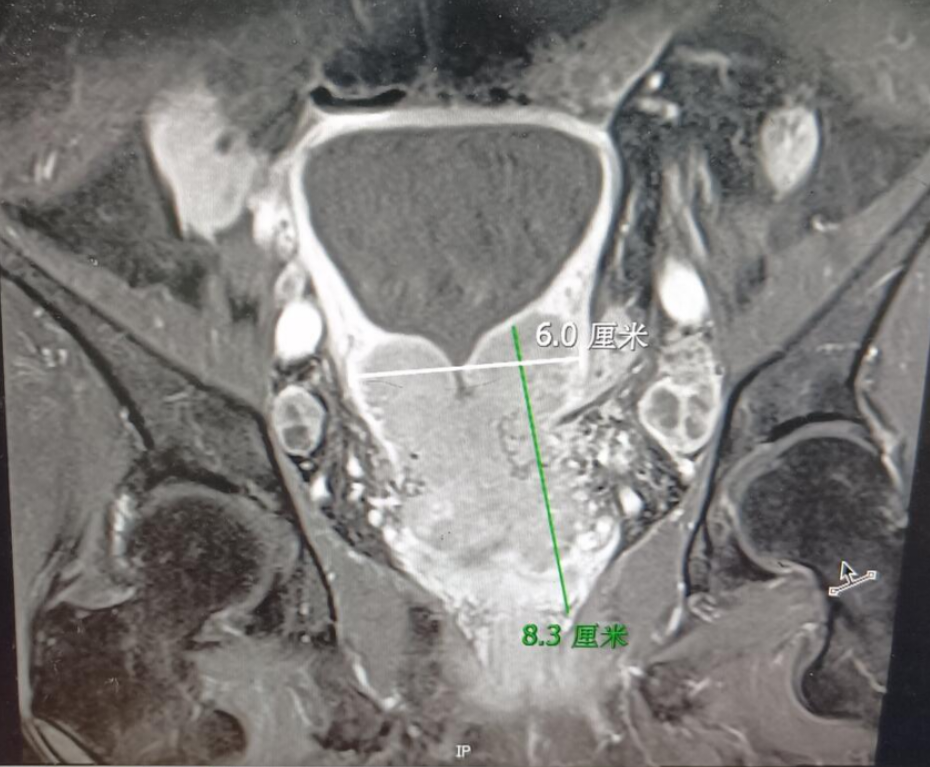

患者62岁,绝经12年,查体发现宫颈异常就诊。妇科检查见外阴阴道无异常,宫颈呈菜花样改变,质硬,约4厘米大小,活动受限,三合诊检查:直肠粘膜光滑,直肠前可触及质硬肿物,未达盆壁,左侧骶韧带弹性差,指套无血迹。2024-12-10TCT:HSIL(鳞状细胞癌不除外)/HPV16(+)/阴道镜检查和活检:(宫颈管组织、宫颈3、12点)浸润癌,倾向鳞状细胞癌。